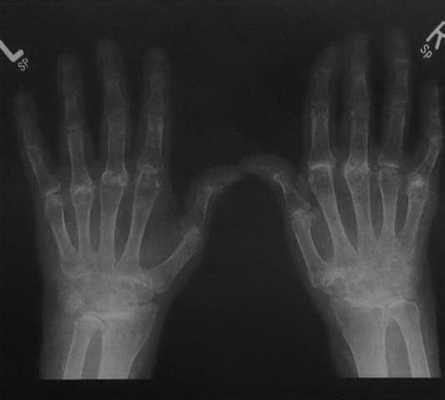

Длительно текущий ревматоидный артрит. Рентгенологическое исследование обеих кистей рук. Генерализованная остеопения. Симметричная структура поражения запястья, пястно-фаланговых суставов и незначительное поражение проксимальных фаланговых суставов. Полная деструкция сустава в некоторых местах или только сужение суставной щели. Вторичные дегенеративные изменения. Уменьшение высоты запястья с левой стороны и локтевое смещение запястья